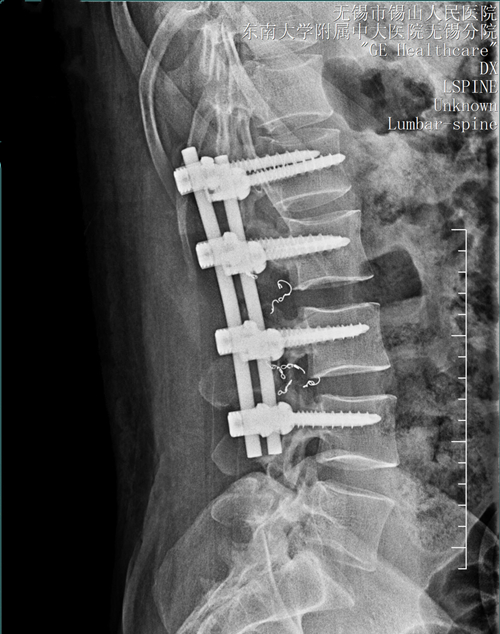

考虑到直接手术切除将导致较多出血,在正式开展手术切除前,介入外科为患者先行腰2-3腰动脉造影+部分栓塞术。两天后,骨科团队为他实施了后路腰2-3附件肿瘤切除+椎管减压+钉棒固定+取髂骨植骨术,完整切除了肿瘤,椎管得到了减压。整台手术历时2小时45分钟,术中最大程度地控制了出血,手术顺利完成。术后,患者腰痛、下肢麻木的症状完全消失,一周后顺利出院。病理检查进一步明确诊断为动脉瘤样骨囊肿,与术前、术中的诊断完全相符。